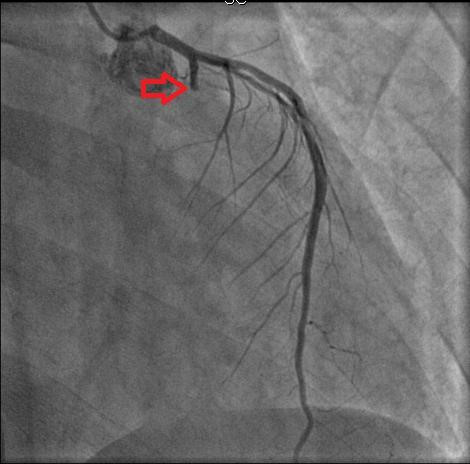

| Hình ảnh chụp mạch vành trước khi đặt stent cho thấy nhánh mũ tắc hoàn toàn từ LCX1. Ảnh: BVCC. |

Sau đó, các bác sĩ can thiệp một stent mạch vành có phủ thuốc trên LCX1 cùng liệu trình điều trị chuẩn của NMCT.